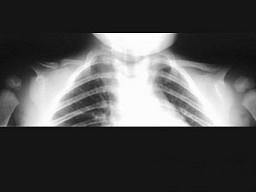

问题 男,2岁,发育迟缓,头颅软,请结合图像,选出最可能的诊断 ( )

选项 A、软骨发育不全 B、粘多糖病 C、颅锁骨发育不全 D、马方综合征 E、成骨不全

答案 C